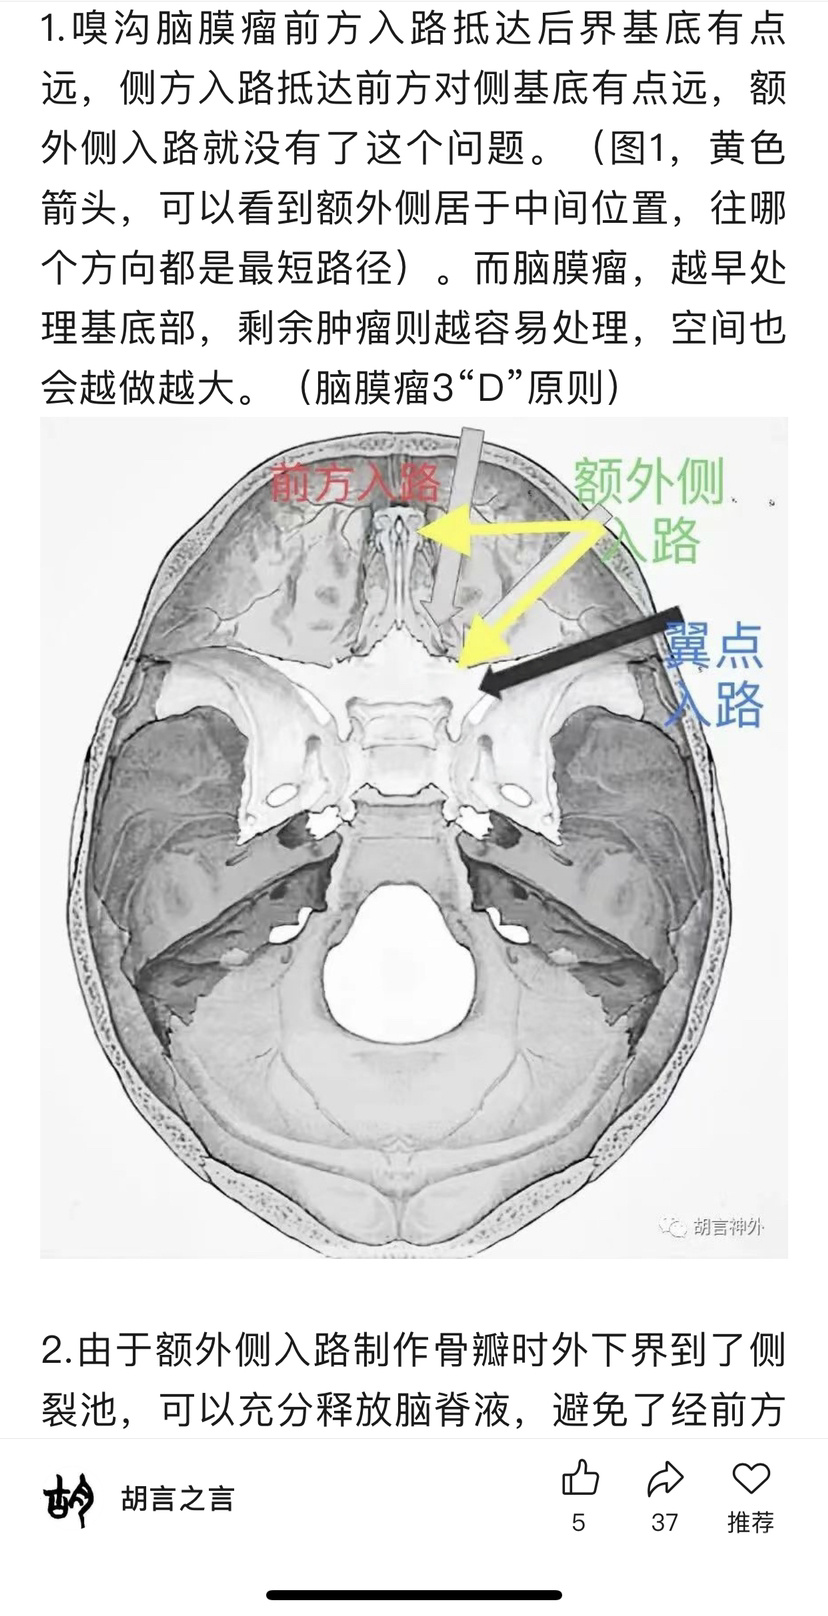

开颅术前参考文献阅读

为方便大家查找原文,特备注公众号信息:2022年03月05日 注册“胡言神外”2025年02月27日 “胡言神外”改名“胡言之言”。(声明:截图分享纯为方便交流,如有侵权或对作者有不良影响,请联系进行相关内容删除,谢谢!)

双侧入路计划(为降低优势半球损伤风险先右侧处理,实在不好搞再左侧)